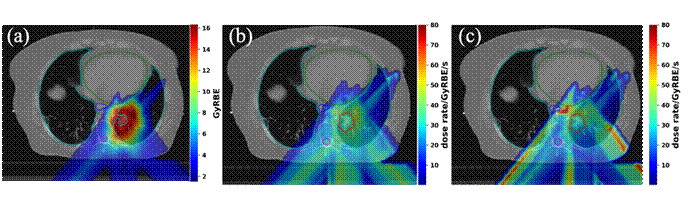

图1:(a)测试病例二维剂量分布 (b)优化前二维剂量率分布 (c)优化后二维剂量率分布

现有的笔型束扫描FLASH放疗研究工作中未考虑充分磁铁扫描顺序对FLASH剂量率的影响。课题组提出了一种通过对扫描路径进行优化从而提升局部剂量率的剂量优化算法。借助这一方法,可以在现有加速器流强限制下,进一步提高危及器官的FLASH剂量率覆盖体积从而更好的保护正常组织,为质子 FLASH 放疗临床计划优化提供了理论基础,也为未来激光加速器治疗计划提供重要借鉴和指导。